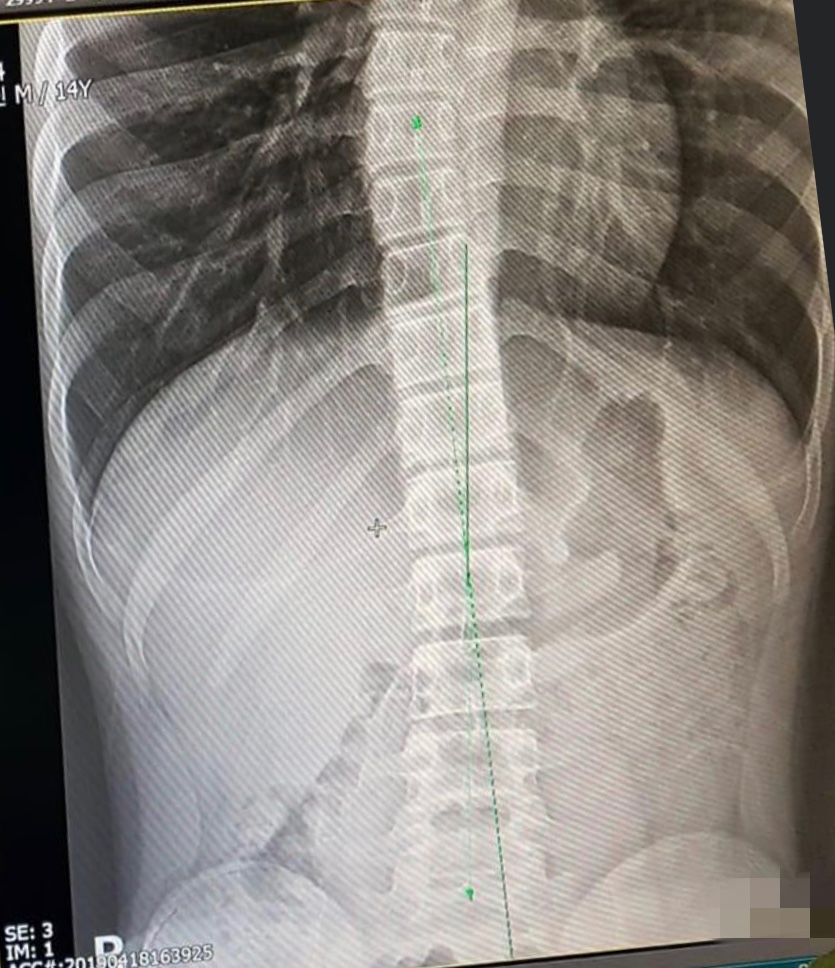

애덤스 전방 굴곡 검사[74]나 스코리오미터[75]를 사용하여 척추측만증을 진단할 수 있다. 척추측만증이 의심되면, 체중 부하 상태에서 척추 전체의 전후면(AP)/관상면 X-레이(정면-후면) 및 시상면 X-레이(측면)를 촬영하여 척추측만증의 만곡과 후만증, 전만증을 평가한다.[76] 성장기 환자의 경우, 곡선 진행을 추적하기 위해 3~12개월 간격으로 척추 방사선 촬영을 하며, 필요한 경우 MRI 검사를 통해 척수를 관찰한다.[76]

콥 각도는 척추 만곡의 정도를 측정하는 표준 방법으로, 관련된 가장 위쪽 척추의 상단 종판에 수직으로 그려진 두 선과 관련된 가장 아래쪽 척추의 하단 종판 사이의 각도를 측정한다. 척추측만증 연구 학회(SRS) 등에서는 관상면에서 10° 이상의 콥 각도를 척추측만증으로 정의한다.[83]

렌트겐 사진 등에서 만곡의 정도(콥 각/Cobb angle)를 측정하여 대략

- 경도(25도 미만)

- 중도(20도~40도 정도)

- 고도(50도 이상)

의 세 단계로 분류하며, 경도에서는 정기적인 X선 촬영을 통한 경과 관찰을 지속한다.